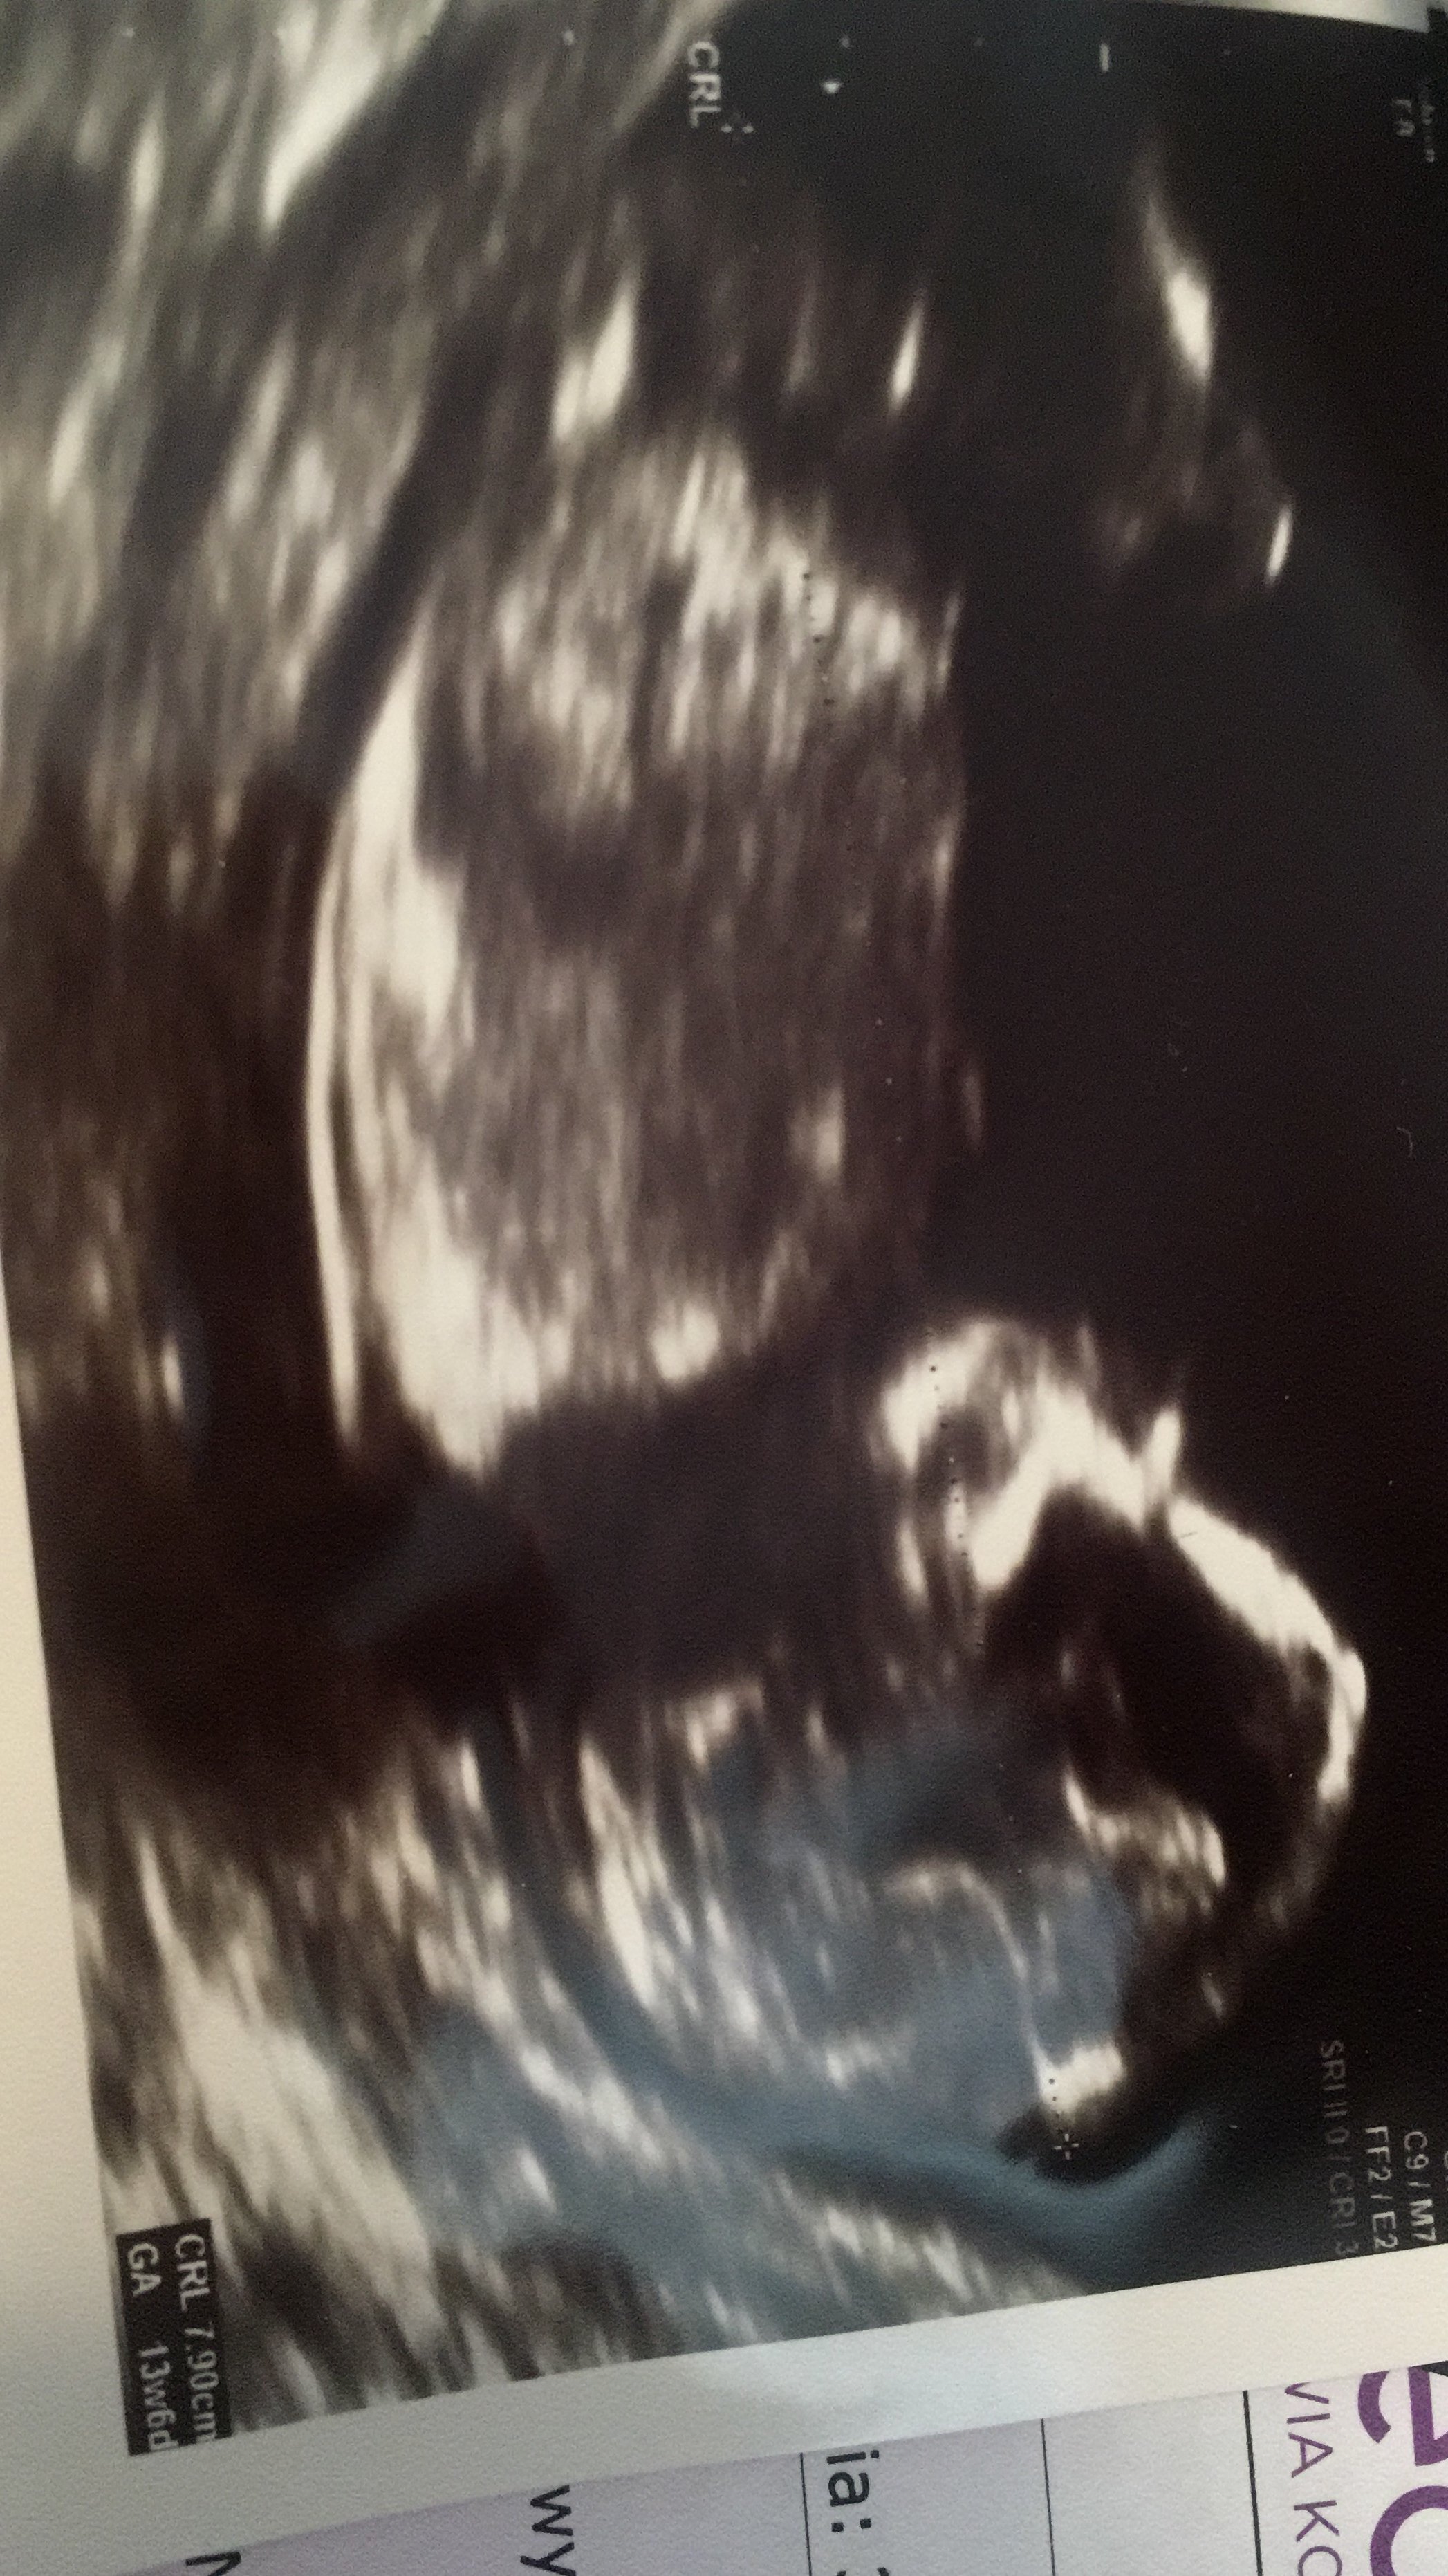

Nie wiem czy uda mi się wstawić zdjęcie. Ale lekarz jest przekonany że syn. No i ze zdjecia widać że syn :p Wytłumaczyl co i gdzie, dla ułatwienia podpisałam :p 12 tydzień i 4 dzień.

• IMG_20181015_170629.jpg

IMG_20181015_170629.jpg

1,3 MB · Wyświetleń: 587

Meggi to zdjecie to tzw potty shot czyli zdjecie rozkroku dziecka od dolu puekbie widac siusiaka;p mam wlasnie takie zdjecie corki z tego samego tygodnia tylko ze u niej nic nie odstawalo;p gratuluje synka!

@Maziajka Czyli na pewno syn?:p bo tak niby widać wszystko co ma facet, ale dopuszczam ten 1%, że można jeszcze pomylić. Koleżanka też myślała że będzie syn syn, a potem lekarz powiedział że jednak dziewczynka a na wcześniejszym USG musiała tak ułożyć się pępowina :p